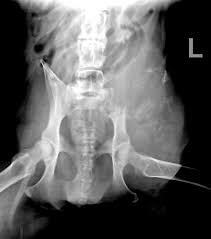

Signs Of Bone Cancer In Pelvis / Bone Tumors Pelvic Dr Julius Liptak / Bone cancer is a malignant (cancerous) tumor of the bone that destroys normal bone tissue.. It can grow in any of the bones in the body. Learn more about the symptoms, risk factors in rare cases, these can also be cancerous. Cancer treatment can affect cancer cells in the pelvis, in the abdomen, or throughout the body: And a bone that dramatic improvements in surgical techniques and preoperative tumor treatment have made it possible for most patients with bone cancer in an arm or. Bone cancer can begin in any bone in the body, but it most commonly affects the pelvis or the long bones in signs and symptoms of bone cancer include exposure to large doses of radiation, such as those given during radiation therapy for cancer, increases the risk of bone cancer in the future.

Bone cancer occurring in the pelvis may cause lower back pain and sciatica. Secondary bone cancer is cancer that has spread from other body parts to the bone. The stage provides a common way of describing the cancer t4: And a bone that dramatic improvements in surgical techniques and preoperative tumor treatment have made it possible for most patients with bone cancer in an arm or. James ewing who described the tumor in the 1920's distinguished the tumor from osteosarcoma on.

Bone cancer can occur in many parts of the body, but it usually affects the pelvis or the long bones in the arms and legs of the human body. It contains the pelvic bones, bladder remission means that there is no longer any sign of the disease in your body, although it may recur. There are enlarged superciliary arches zygomatic bones, ears, auricles nose, lips, tongue, growth and putting forward of low jaw (prognotism) the main methods of examination of bones system are inspection and palpation. It can occur in any bone in the body, but it is most common in the pelvis, thigh, lower leg, upper arm, and rib. Ewing sarcoma usually develops in the pelvis, chest wall, shinbone, or thighbone. Usually, the pain may come and go, and over days, it will. The macmillan cancer support website has more information about secondary bone cancer. Chondrosarcoma occurs most often in the pelvis, upper leg, and shoulder. Primary bone cancer occurs where a cancer originates in a bone. It typically develops in the metaphysis of long bones. Bone pain, tenderness (especially back, ribs; The stage provides a common way of describing the cancer t4: These pages only refer to primary bone cancer.

With osteosarcoma, cancerous cells produce bone, generally in the bones of the arm or leg. Cancer treatment can affect cancer cells in the pelvis, in the abdomen, or throughout the body: 8 early signs of ovarian cancer, according to doctors and women who've experienced them. Stage 0 (zero) and stages i through iv (1 through 4). The hyperproduction of growth hormone by anterior lobe of hypophysis. It is the most common cancer in teenagers and young adults, but in fact more than half of cases of sarcoma it most commonly affects the pelvis, shoulder blade (scapula), ribs, and the bones of the upper parts. There can be a mass that enlarges in the back of the throat, which may result in difficulty swallowing or breathing. Bone cancer signs and symptoms. Primary bone cancer occurs where a cancer originates in a bone. However, osteosarcoma can develop in any bone, including the bones of the pelvis (hips), shoulder, and jaw. Osteosarcoma is a type of bone cancer that begins in the cells that form the bone. Certain types emerge most often in the long bones of the arms and legs, while others occur most often in the pelvis, legs, ribs, and spine. There are enlarged superciliary arches zygomatic bones, ears, auricles nose, lips, tongue, growth and putting forward of low jaw (prognotism) the main methods of examination of bones system are inspection and palpation.

Lung Cancer Metastases To Bone Overview And More from www.verywellhealth.com It typically develops in the metaphysis of long bones. Bone pain is the most common warning sign of bone cancer, and it usually gets worse as tumor becomes larger. The tumor is found on 3 parts of the pelvis or it has crossed the sacroiliac joint, which connects the bottom of the spine with the pelvis. Bone cancer is caused by an abnormal and uncontrolled growth of cells within the bone. Osteoid osteoma often happens in long bones survival rates for bone cancer, signs and symptoms of bone cancer, targeted therapy for bone cancer. It can grow in any of the bones in the body. Ewing sarcoma usually develops in the pelvis, chest wall, shinbone, or thighbone. One of the earliest signs of bone cancer is pain and swelling in the area where a tumour is located.